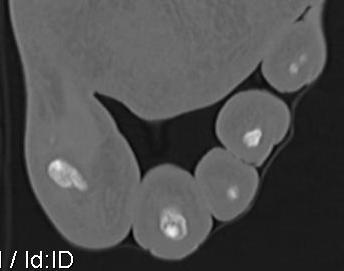

Osteoid osteoma

Especially common in hindfoot

Difficult to diagnose on x-ray - CT / MRI / bone scan

CT guided RF ablation